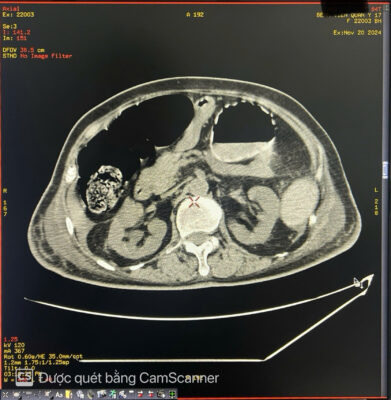

🚑 Một phụ nữ 84 tuổi đến khám với tình trạng đau bụng kèm táo bón mãn tính lâu ngày. Khi khám, bụng căng to, nhiều hơn ở bên trái. Sờ thấy một khối u mơ hồ ở hố chậu trái. Chụp X-quang bụng không chuẩn bị cho thấy giãn đại tràng lên và đại tràng ngang, toàn bộ đại tràng xuống chứa đầy phân. Các quai ruột non bị di lệch sang bên phải bụng. Siêu âm bụng thấy bụng căng nhiều hơi. Chụp cắt lớp vi tính (CT) ổ bụng cho thấy đại tràng xuống và đại tràng sigma giãn lớn chứa đầy phân kèm vôi hóa không đều tạo thành một khối u phân trong lòng đại tràng, có kích thước # 8 x9 x 26cm. Đại tràng lên và đại tràng ngang giãn d# 6.4 cm. Hai thận ứ nước độ I. Thành đại tràng dày nhẹ, còn cấu trúc lớp, thâm nhiễm mỡ nhẹ xung quanh, kèm ít dịch hạ vị. Không thấy khối u hoặc hẹp lòng ruột cản trở ở vùng trực tràng-sigma. Bệnh nhân được điều trị bảo tồn bằng thụt tháo và thuốc nhuận tràng. Hiện tại bệnh nhân ổn định, các triệu chứng cải thiện rõ rệt.

Hình ảnh 3 Hình ảnh 4 Hình ảnh 5

👉 Tóm lại: U phân là một dạng tắc nghẽn phân nghiêm trọng. U phân được hình thành do tình trạng ứ đọng phân trong đại tràng kéo dài, theo thời gian, các chất cặn bã này sẽ được sắp xếp lại để tạo thành một khối phân cứng, có hình dạng rõ ràng trong lòng đại tràng. Cũng có thể thấy vôi hóa. Đại tràng sigma và trực tràng là những vị trí thường gặp của u phân. U phân thường gặp ở bệnh Hirschsprung, bệnh Chagas, bệnh nhân nội trú bị chấn thương cột sống, bất thường về hành vi và ở bệnh nhân cao tuổi bị táo bón mãn tính. Các biến chứng của u phân bao gồm tắc ruột, loét đại tràng và thận ứ nước do ảnh hưởng của khối. Các lựa chọn điều trị bao gồm sử dụng thuốc thụt, thuốc nhuận tràng và làm sạch trực tràng để giảm tình trạng tắc nghẽn phân và can thiệp phẫu thuật nếu các phương pháp bảo tồn không hiệu quả.